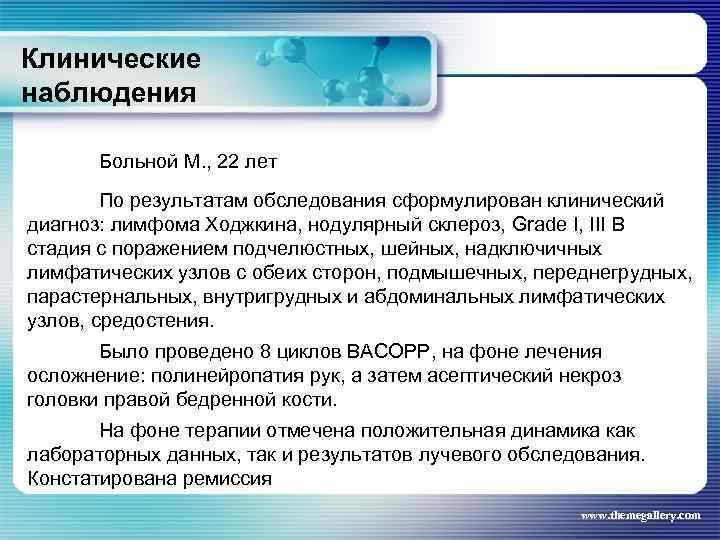

Клинические наблюдения Больной М. , 22 лет По результатам обследования сформулирован клинический диагноз: лимфома Ходжкина, нодулярный склероз, Grade I, III В стадия с поражением подчелюстных, шейных, надключичных лимфатических узлов с обеих сторон, подмышечных, переднегрудных, парастернальных, внутригрудных и абдоминальных лимфатических узлов, средостения. Было проведено 8 циклов BACOPP, на фоне лечения осложнение: полинейропатия рук, а затем асептический некроз головки правой бедренной кости. На фоне терапии отмечена положительная динамика как лабораторных данных, так и результатов лучевого обследования. Констатирована ремиссия www. themegallery. com

Клинические наблюдения Больной М. , 22 лет По результатам обследования сформулирован клинический диагноз: лимфома Ходжкина, нодулярный склероз, Grade I, III В стадия с поражением подчелюстных, шейных, надключичных лимфатических узлов с обеих сторон, подмышечных, переднегрудных, парастернальных, внутригрудных и абдоминальных лимфатических узлов, средостения. Было проведено 8 циклов BACOPP, на фоне лечения осложнение: полинейропатия рук, а затем асептический некроз головки правой бедренной кости. На фоне терапии отмечена положительная динамика как лабораторных данных, так и результатов лучевого обследования. Констатирована ремиссия www. themegallery. com